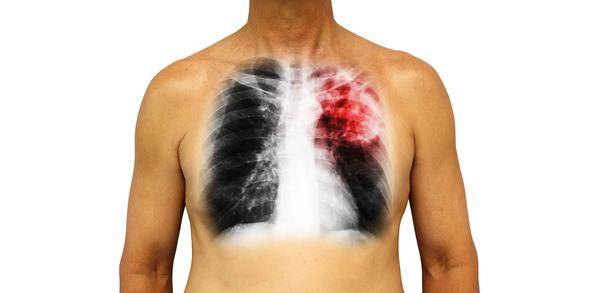

肺癌的發生除了和遺傳因素有關以外,日常的生活習慣也會影響到肺癌的發生;

在患有肺癌以後,患者會出現咳嗽、咳痰、咳血等症狀,如果得不到及時有效的救治,還會危害到生命的安全,因此日常一定要注意肺癌的預防。